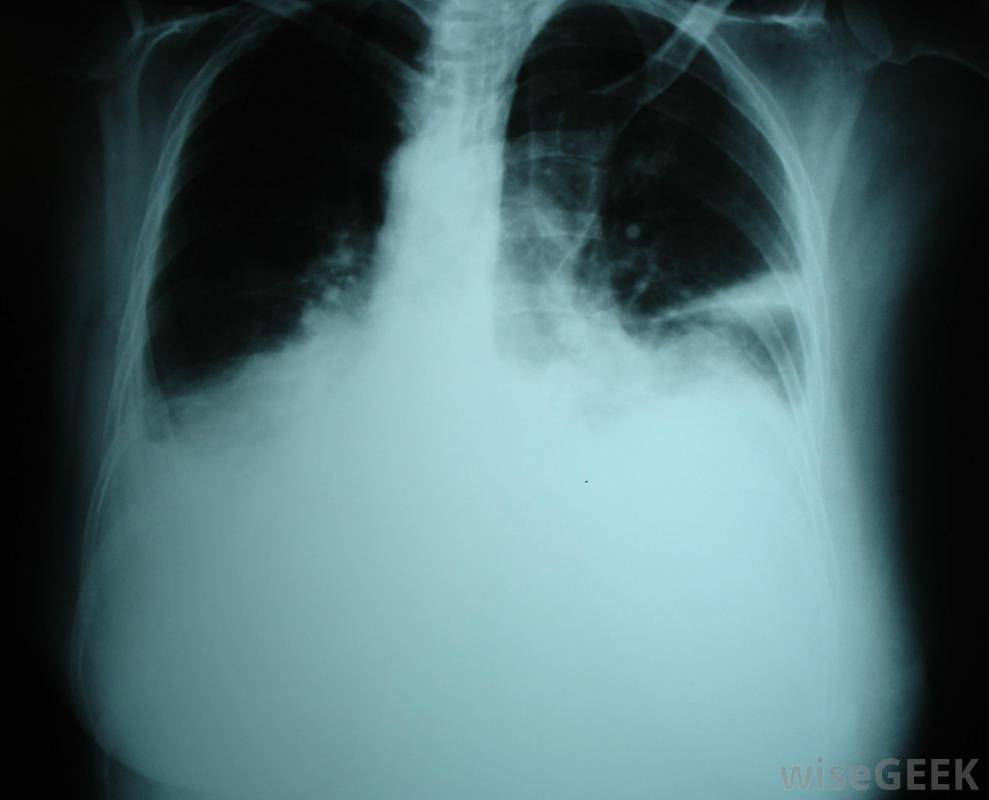

Fontan手術是一種姑息性的醫療手術,心臟的右心房直接與肺動脈相連,繞過右心室。這種手術通常用于患有先天性心臟缺陷的兒童,包括三尖瓣閉鎖、肺動脈閉鎖、心臟發育不全綜合征,單左心室,雙出口右心室,以及任何其他單心室缺陷或先天性心臟缺陷只留下一個功能心室。Fontan手術允許血液被動地從心房進入肺動脈,肺動脈將血液輸送到肺部以獲得再充氧,而不是通過作為一種姑息性的治療方法,它可以幫助病人克服缺陷,但不能治愈病情。Fontan手術的目標是心臟;右心房。正常心臟有四個心室:右心房、右心室、左心房和左心室。右心房接受去氧,"用完"的血液通過下腔靜脈和上腔靜脈進入右心室,在右心室被泵入肺動脈。肺動脈將血液輸送到肺部以獲得再充氧,然后血液通過肺靜脈回到心臟的左心房,然后血液進入左心室,在那里被泵出進入主動脈,將含氧血液輸送到身體其他部位Fontan手術是對一個有缺陷的人進行的,右心室的功能是將血液輸送到肺部,胸腔積液是肺部積液的一種并發癥有幾種缺陷,通常是由妊娠前8周的發育問題引起的,可導致這種情況。在三尖瓣閉鎖中,使血液從心房流向心室的三尖瓣不能形成,在左心發育不良綜合征(HLHS)中,左心室不能正常發育,所以左心室通常很小或根本不存在。右心發育不良綜合征(HRHS)是一種與HLHS相似的不太常見的疾病,但右心室有缺陷,左心室功能正常在一個或兩個心室中,一個或兩個心臟瓣膜不能正常連接,左心室。如果Fontan手術不能改善患者的健康狀況,則可能需要進行心臟移植Fontan手術通過繞過右心室,直接從右心房向右心室采血,使血液進入肺部,而不會使單個功能心室過度工作。手術通常分為兩個階段,即半Fontan手術,也稱為雙向Glenn手術,在半閉穴期,肺動脈和上腔靜脈(SVC)將缺氧的血液從心臟輸送到肺,上腔靜脈(SVC)將缺氧的血液從上半身輸送到心臟,與心臟斷開。SVC與肺動脈相連,因此,缺氧的血液直接流向肺部,下腔靜脈(IVC)將缺氧的血液從下體輸送到心臟,與心臟保持連接,因此這些血液不會再獲得氧氣。右心房通過下腔靜脈和上腔靜脈接受來自身體的去氧血液,患者可以只接受Fontan手術的前半部分,但他們經常缺氧,或者血液供氧不足,因為來自下腔靜脈的血液沒有被重新充氧,Fontan完成后,下腔靜脈的血流從流向心臟轉向直接流向肺部,這使得孩子能夠正常生長,避免對疾病的易感性增加下腔靜脈將缺氧的血液從下體輸送到心臟。Fontan手術通常在嬰兒兩歲以后進行,由于高血管阻力或血液通過循環系統需要大量的工作,嬰兒往往不能忍受手術。并發癥可能包括感染、胸腔積液、肺部積液和心房顫動。這些并發癥可能需要短期或長期用藥,胸導管和外科手術。在某些情況下,Fontan手術可能不能充分改善患者的健康和生活質量,患者可能需要心臟移植。然而,對于許多患者來說,手術可以使孩子正常發育并過上正常、健康的生活使用Fontan程序,右心房直接與肺動脈相連。Fontan手術通常用于先天性心臟病。